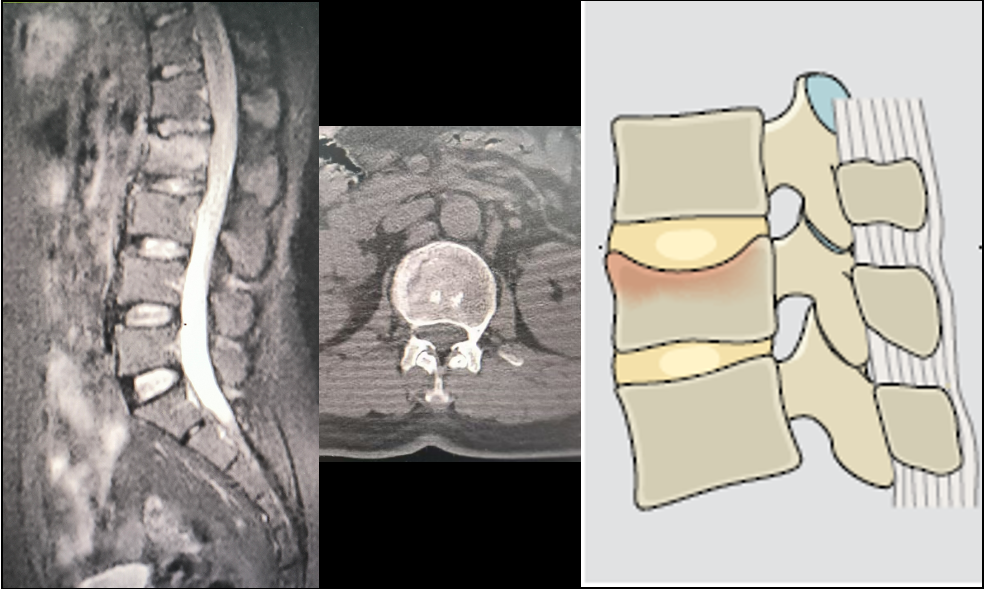

MRI与CT显示:第2腰椎压缩性骨折